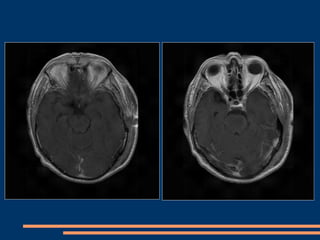

IRM post-opératoire à J 15

IRM post-opératoire à 3 mois

IRM post-opératoire  3 mois